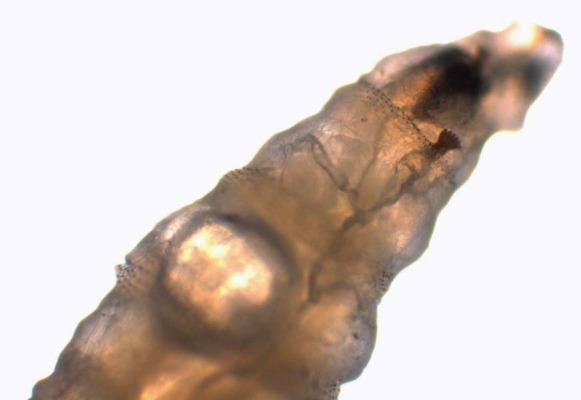

Myiasis is the infestation of living bodies of animals and humans with fly larvae or maggots. These accidental or obligatory parasites grow in three stages in the host while feeding on his tissues. Myiasis in a hospital area is a rare situation when flies accidentally lay their eggs on patients, mostly in open wounds or cavities. Case presentation. We report a case of a 72-year-old patient admitted to a general surgery department for peritonitis, then to an intensive care unit (ICU) for septic shock where he was intubated. Some maggots were seen moving in his nasal cavity a few days after his admission and were sent to our laboratory for examination. The larvae were identified as the third larval stage of sp. They were removed entirely after intense nasal washing. A checking examination of his nasal cavities revealed no evidence of further infestation. After nasal washing, no other larvae were seen but unfortunately, the patient died of septic shock a few days later.

Few cases of nasal myiasis in hospitalized patients were reported. ICU myiasis, extremely rare, is caused by the patient's inability to fend off the flies because of their conscious state, presence of blood or odors caused by infections, and the warm humid environment.